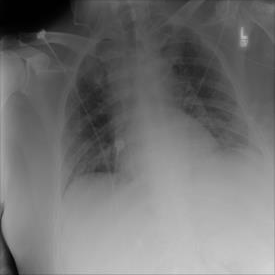

The COVID-19 disease was first discovered in Wuhan, China, and spread quickly worldwide. After the COVID-19 pandemic, many researchers have begun to identify a way to diagnose the COVID-19 using chest X-ray images. The early diagnosis of this disease can significantly impact the treatment process. In this article, we propose a new technique that is faster and more accurate than the other methods reported in the literature. The proposed method uses a combination of DenseNet169 and MobileNet Deep Neural Networks to extract the features of the patient's X-ray images. Using the univariate feature selection algorithm, we refined the features for the most important ones. Then we applied the selected features as input to the LightGBM (Light Gradient Boosting Machine) algorithm for classification. To assess the effectiveness of the proposed method, the ChestX-ray8 dataset, which includes 1125 X-ray images of the patient's chest, was used. The proposed method achieved 98.54% and 91.11% accuracies in the two-class (COVID-19, Healthy) and multi-class (COVID-19, Healthy, Pneumonia) classification problems, respectively. It is worth mentioning that we have used Gradient-weighted Class Activation Mapping (Grad-CAM) for further analysis.

翻译:COVID-19 疾病在中国武汉首次发现,并迅速蔓延到全世界。在COVID-19 流行病后,许多研究人员开始寻找一种方法,利用胸前X光图像诊断COVID-19 。早期诊断该疾病可以大大影响治疗过程。在本篇文章中,我们提出了一种比文献中报告的其他方法更快和更准确的新方法。拟议方法使用DenseNet169 和移动网络深神经网络的组合来提取病人X光图像的特征。在使用单向特征选择算法后,我们改进了最重要的特征。然后,我们将选定特征用作对光GBM(轻度推动机)算法的投入。为评估拟议方法的有效性,使用了ChestX-光8 数据集,其中包括病人胸部的1125 X光图像。拟议方法在两类(COVID-19,健康价值)和多级(COVID-19)中达到了98.54%和91.11%的缩略图。我们分别使用了“高度”的GRAMA-GRA级(C) 分别用于健康等级分析。